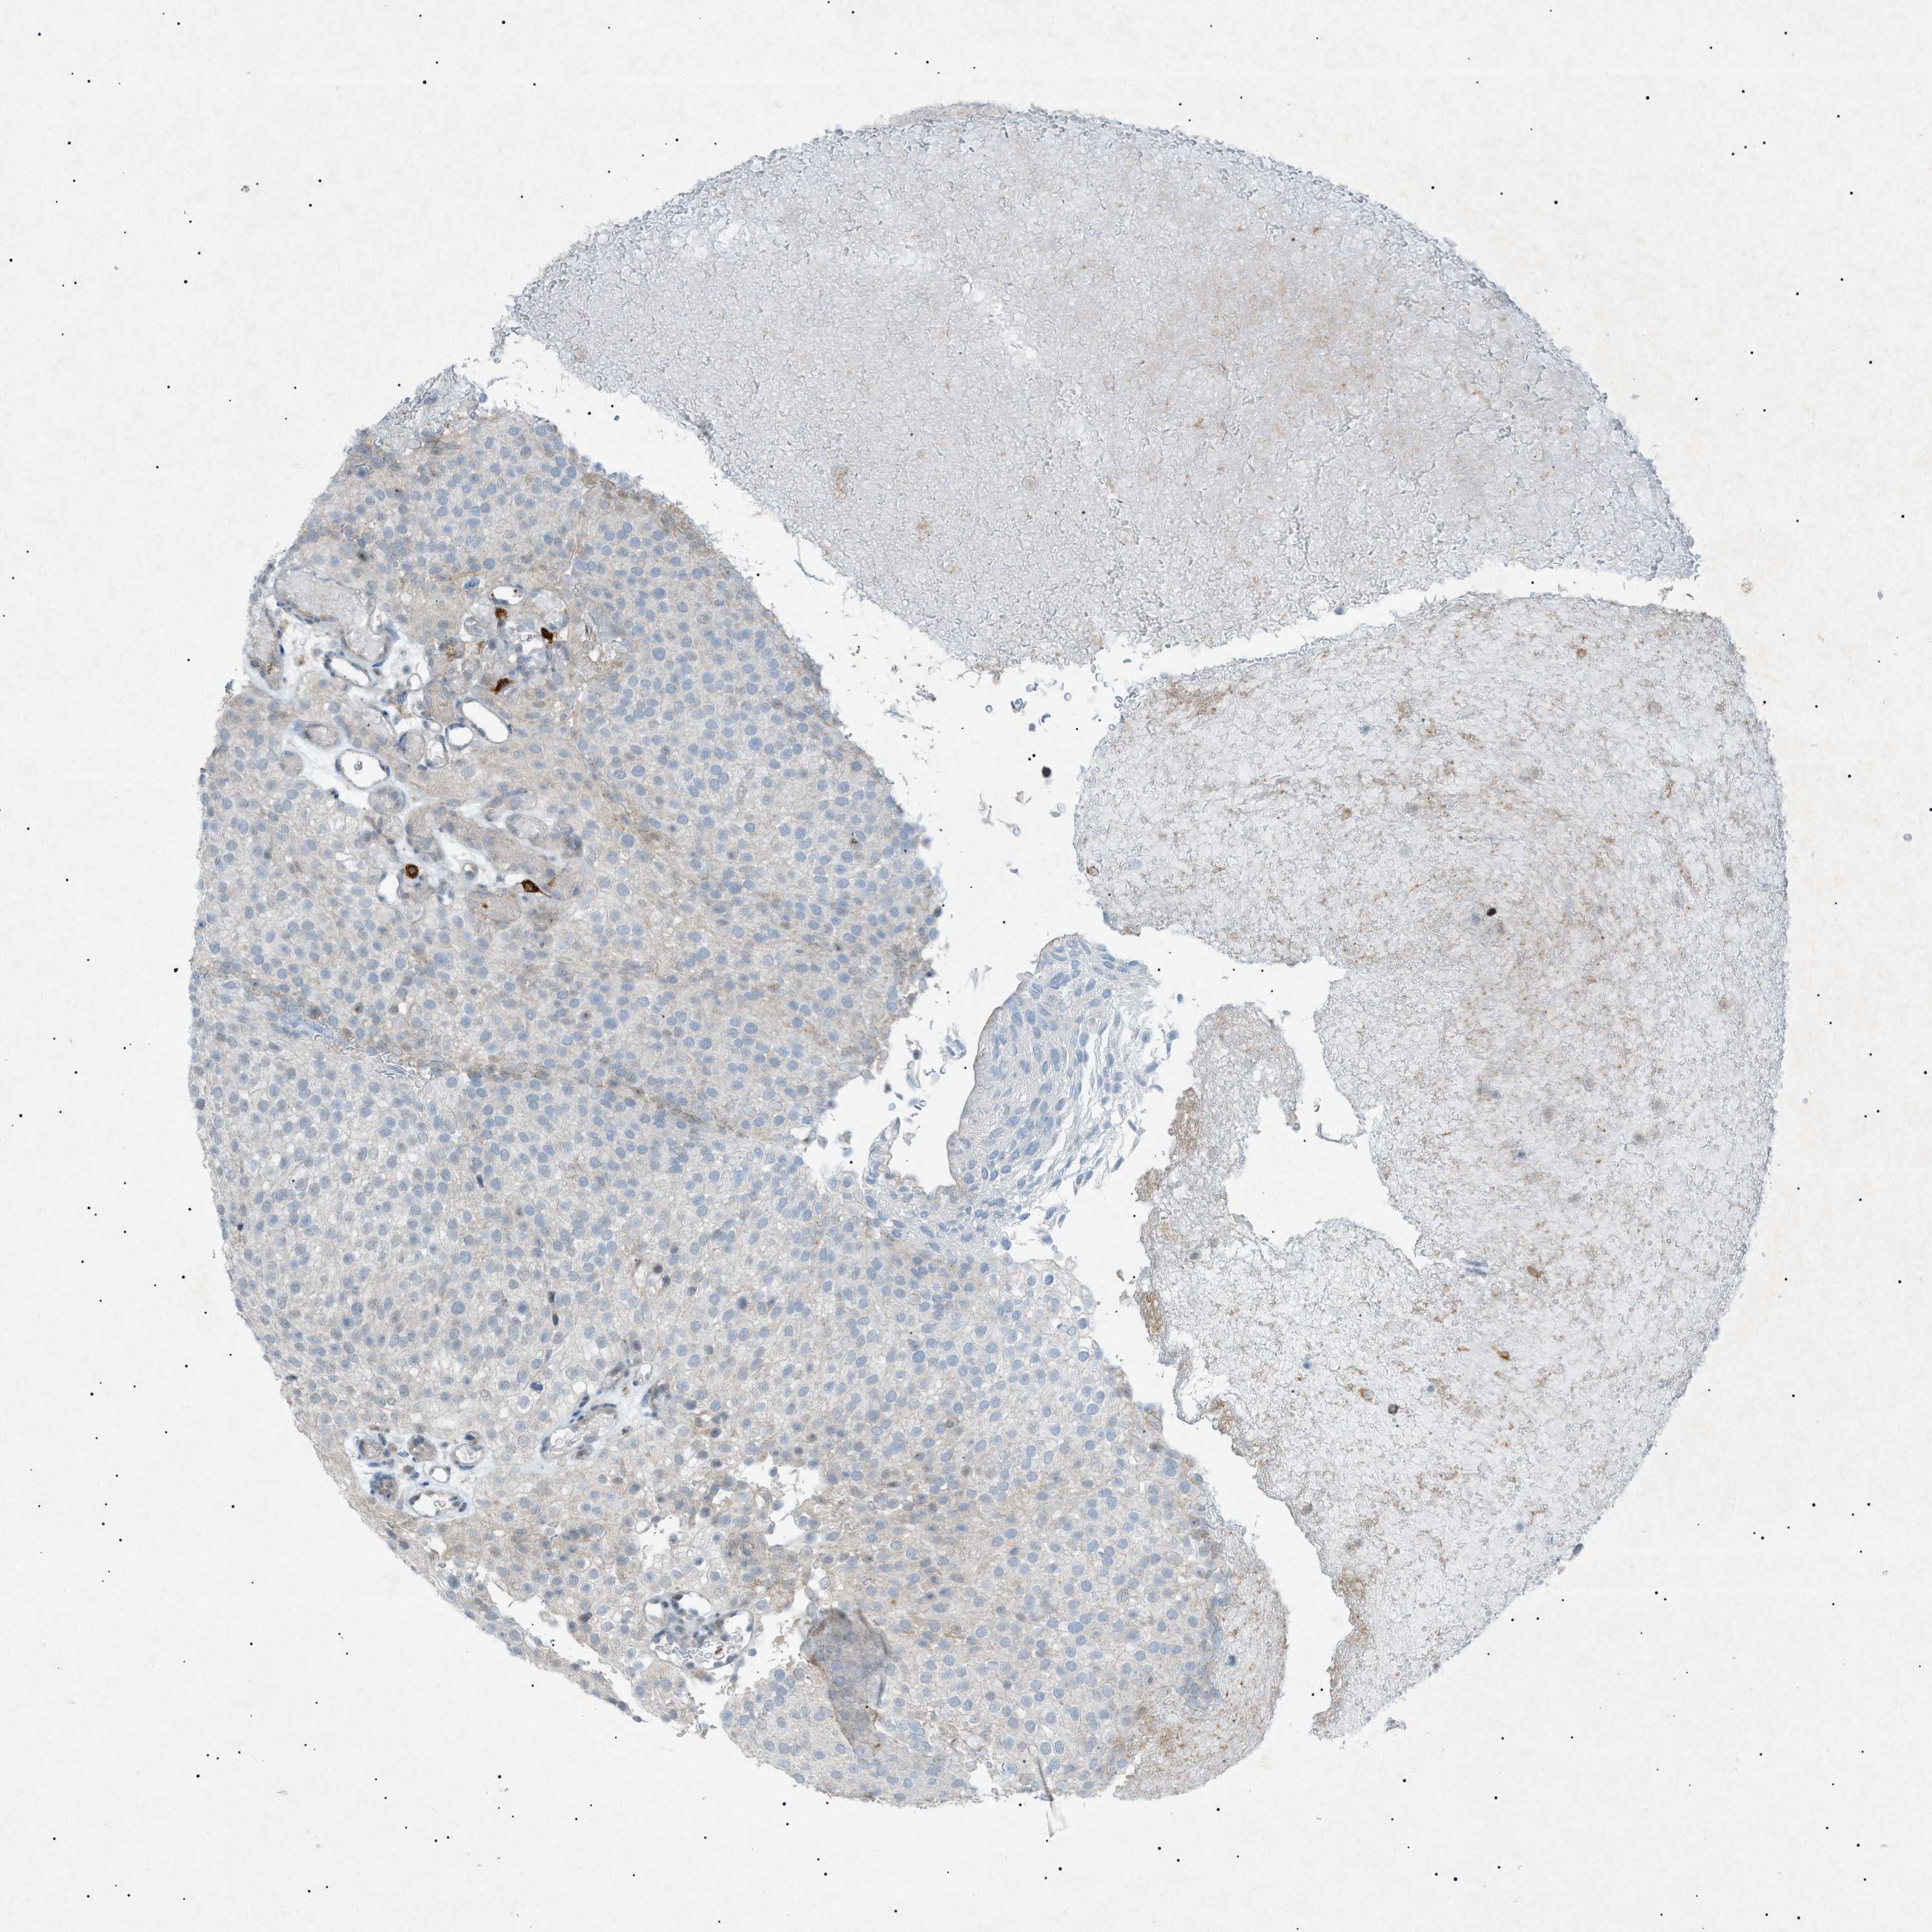

UROTHELIAL CANCER - Protein expressioni

A mouse-over function shows sample information and annotation data. Click on an image to view it in a full screen mode. Samples can be filtered based on level of antibody staining by selecting one or several of the following categories: high, medium, low and not detected. The assay and annotation is described here.

Note that samples used for immunohistochemistry by the Human Protein Atlas do not correspond to samples in the TCGA dataset.

Antibody stainingi

Antibody staining in the annotated cell types in the current human tissue is reported as not detected, low, medium, or high, based on conventional immunohistochemistry profiling in selected tissues. This score is based on the combination of the staining intensity and fraction of stained cells.

Each image is clickable and will lead to virtual microscopy that enables deeper exploration of all samples and also displays staining intensity scores, fraction scores and subcellular localization as well as patient and tissue information for each sample.

Antibody HPA001198

Antibody HPA002028

Antibody CAB016689

Antibody CAB080300

Staining

High

Medium

Low

Not detected

Intensity

Strong

Moderate

Weak

Negative

Quantity

>75%

75%-25%

<25%

None

Location

Nuclear

Cytoplasmic/membranous

Cytoplasmic/membranous,nuclear

Urothelial carcinoma, High grade

Urothelial carcinoma, Low grade

Adenocarcinoma, NOS